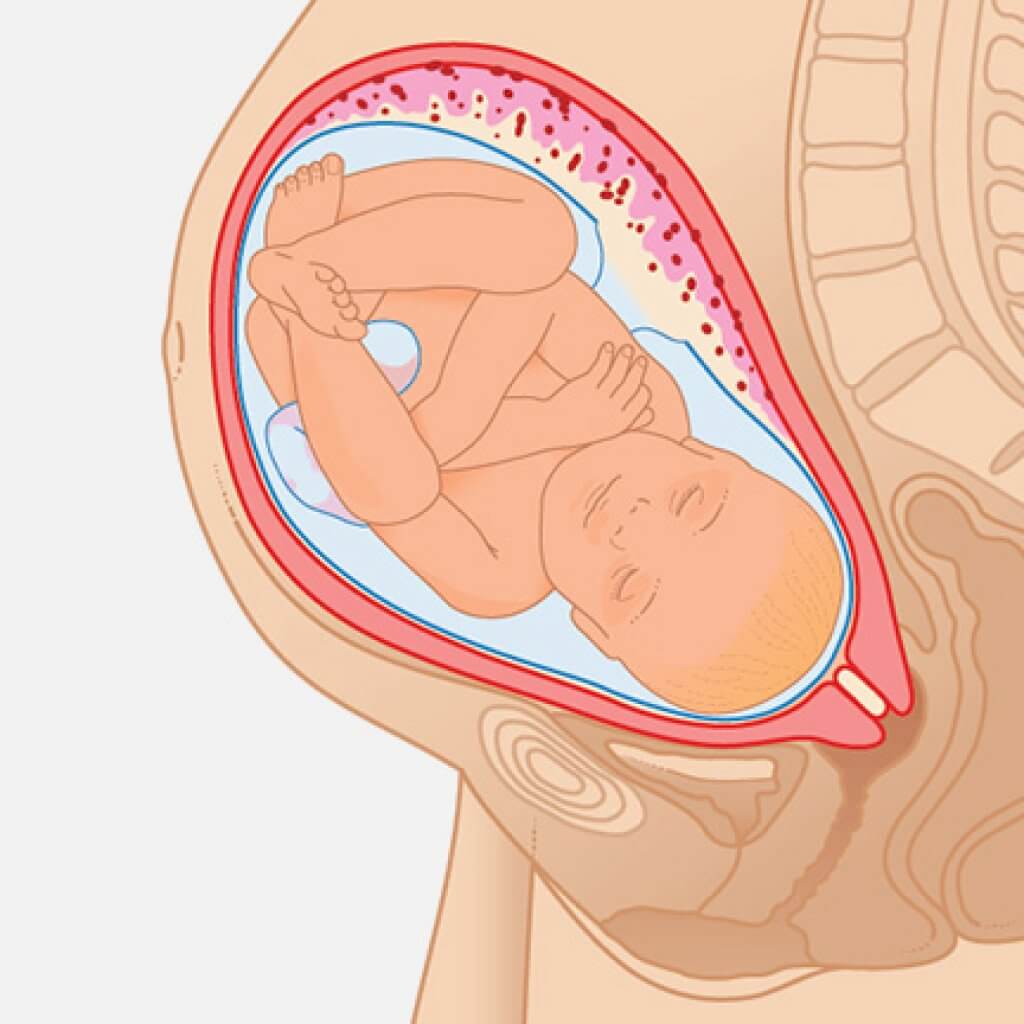

Плод 39 Недель Фото

Плод 39 Недель Фото 100 фото